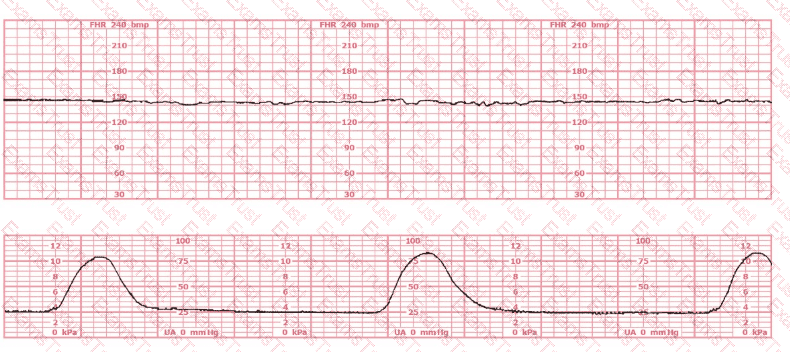

This tracing is consistent with: